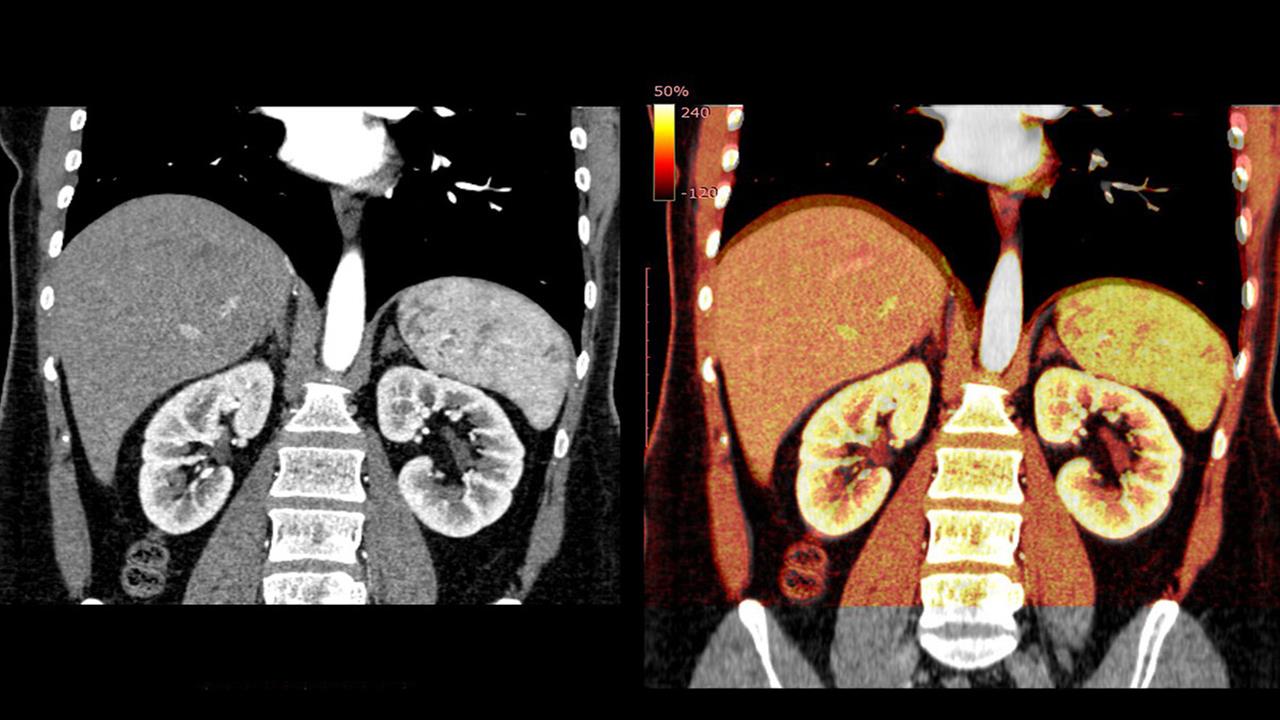

Τα ποδοκύτταρα αποτελούν σημαντικό συστατικό του λεγόμενου φραγμού αίματος-ουρίας. Στα περίπου ένα εκατομμύριο σπειράματα των νεφρών, καλύπτουν την επιφάνεια των αιμοφόρων αγγείων με τα "ποδαράκια" τους και λειτουργούν ως φίλτρο που επιτρέπει τη διέλευση μόνο ορισμένων ουσιών με χαμηλό μοριακό βάρος (οι πρωτεΐνες γενικά δεν περιλαμβάνονται).

Τα ελαττώματα έχουν ως αποτέλεσμα νεφριτικό σύνδρομο με οίδημα.

Είναι ήδη γνωστές διάφορες δυσλειτουργίες των ποδοκυττάρων που μπορούν να διαταράξουν τη λειτουργία του φίλτρου. Μια προηγουμένως υποτιμημένη αιτία αυτών των ποδοκυτταροπαθειών θα μπορούσε να είναι τα αυτοαντισώματα έναντι της πρωτεΐνης νεφρίνης.